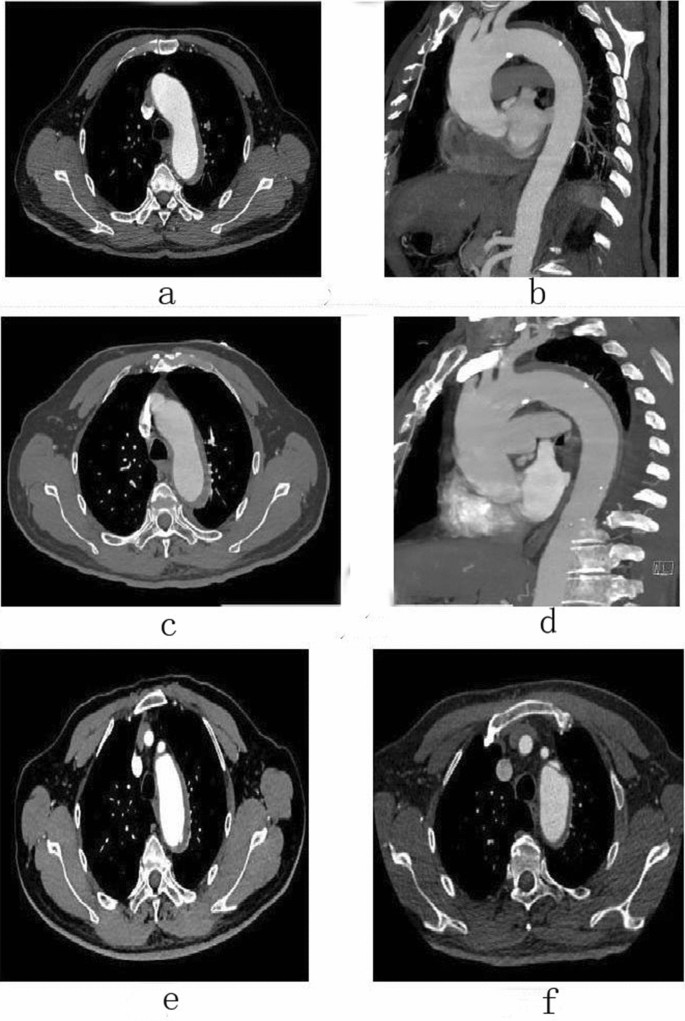

Follow-up

Male, 67 years old, admitted to hospital for “sudden pain in chest for 9 h”, Diagnosis: Stanford type B aortic dissection; Treatment: IMH conservative treatment. CTA of the patient in different periods: (a) Admission; (b) Admission; (c) 3 days after admission; (d) 3 days after admission; (e) 3 months after admission; (f) 11 months after admission.